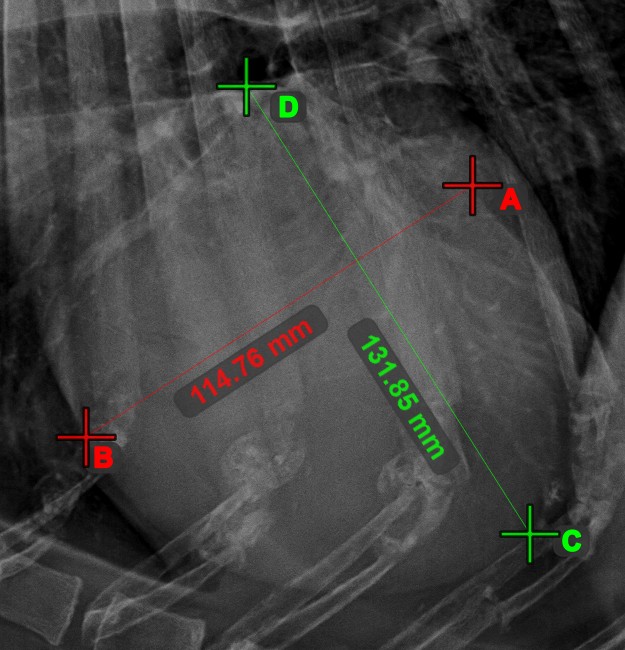

Line Intersection

Quickly and accurately locate and mark the intersection point between two existing lines by using the Line Intersection tool.

Select the tool from the left toolbar and assign it to one of the available mouse buttons. Select two lines that have already been drawn on the scene to complete the measurement. The intersection point of the line will be automatically calculated and marked on the scene. The intersection point of two lines will always be marked with the letter X.

Information

If two lines do not intersect directly, the intersection point of their extended projections on the scene will be marked.

../_images/image408.jpg ../_images/image37.jpg